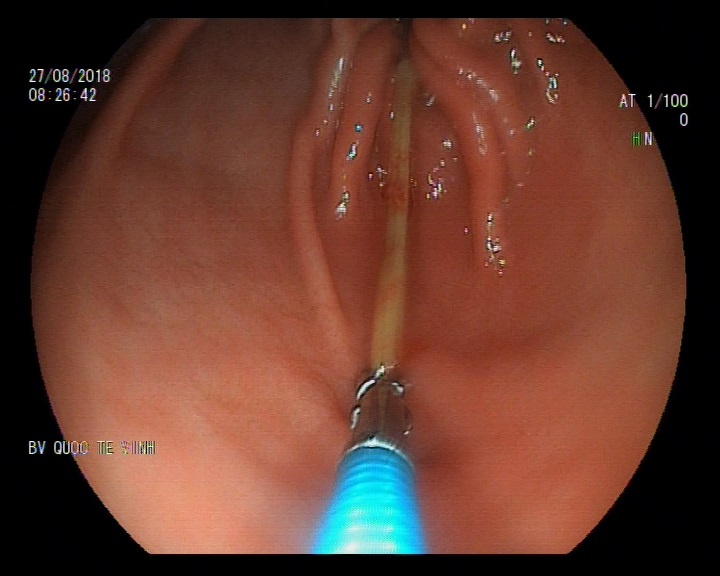

| Hình ảnh thực hiện nội soi dạ dày lấy dị vật ra ngoài. |

Tại đây, qua thăm khám và tiến hành nội soi, các bác sĩ phát hiện có 1 dị vật trong dạ dày của bệnh nhân T. Bác sĩ bệnh viện sau đó nội soi để lấy dị vật ra ngoài. Dị vật đó là 1 cái tăm nhọn dài 7cm.

Theo Bác sĩ Phùng Thị Hằng, Trưởng khoa Nội (Bệnh viện Quốc tế Vinh, là người trực tiếp tiến hành lấy dị vật ra) cho hay, chiếc tăm nằm ở mặt sau hành tá tràng, một đầu nhọn cắm vào thành ruột gây chảy máu.